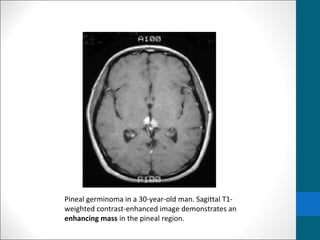

Pineal germinoma in a 30-year-old man. Sagittal T1-

weighted contrast-enhanced image demonstrates an

enhancing mass in the pineal region.

Germinoma …..MRI findings •T1/T2: • Usually isointense relative to cerebral gray matter •Occasionally • T1:hypointense • T2:hyperintense • I/V injection of gadolinium-based contrast material, • homogeneous and intense enhancement is seen. • contrast-enhanced MRI (subarachnoid seeding of germinomas.)